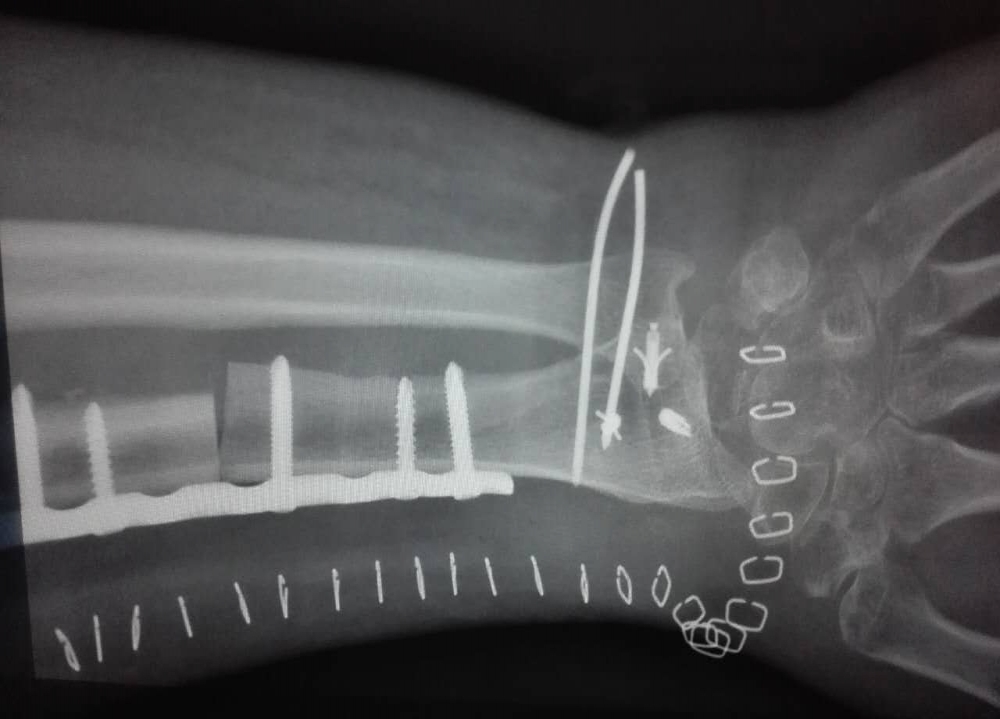

手术已经过去两周了,目前来看恢复状况良好,手指除了大拇指比较僵硬之外基本上恢复活动能力了。 不过手腕里面还打着两根钉子,现在完全动不了,打字也只能单手,码字就别想了。 6 ↑就是竖着那两根。 医生说是术后六周才能拔钉子,也就是说我得下个月20号或者21号才有可能恢复更新了。 另外,我在养病期间重新读了一遍以前写的东西……发现写的挺无趣的,成绩那么烂也是理所当然了,真没想到还能有几百个读者。 等好了以后大概我会全部推翻重写吧,不过在躺尸的时候我又想到了一个点子……又想开新书又想重写好矛盾啊_(:з」∠)_9